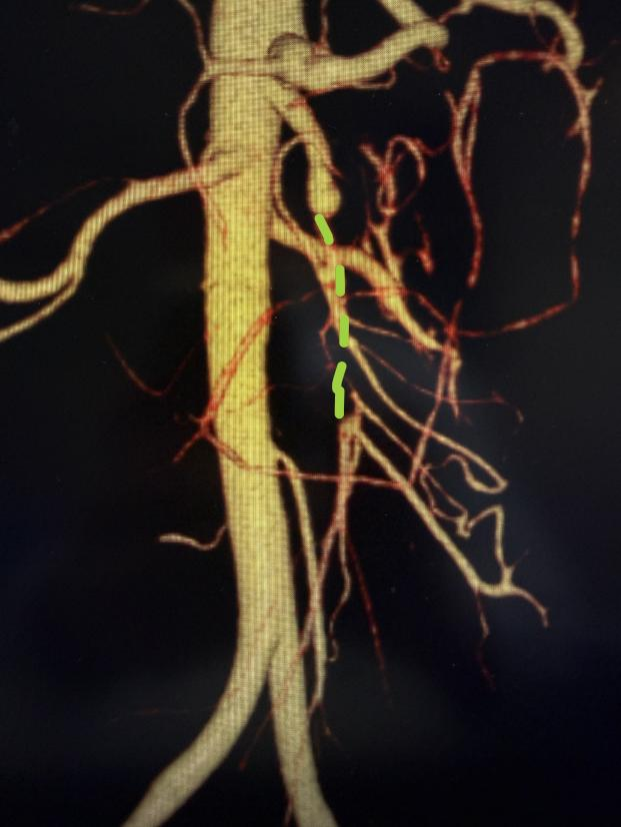

“通过造影可以看到,绿色虚线位置本应是一条相连的血管,如今像是断开了一样,而这段虚线就是被压瘪的血管。危险之处就在于夹层挤压血管真腔,会导致肠道严重缺血甚至坏死,这种情况必须尽快进行介入手术。”王林君向张先生补充道。